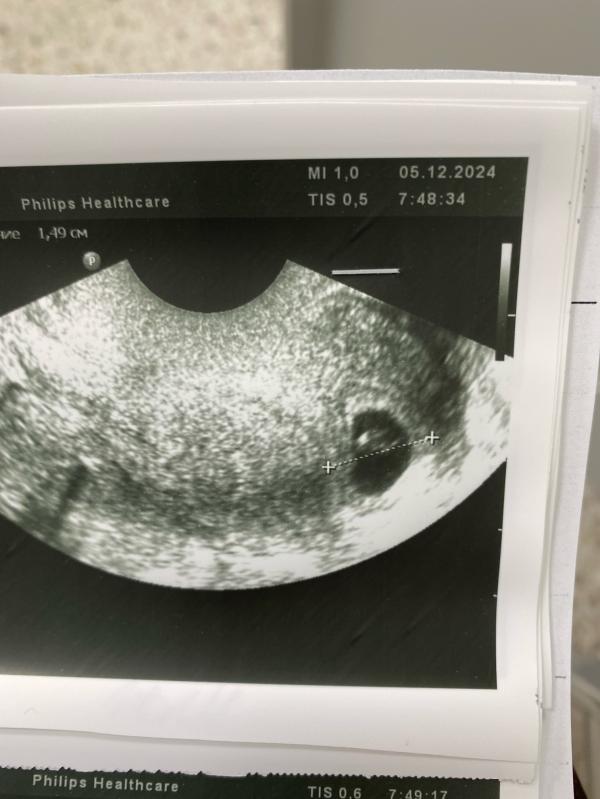

Сегодня пулей летела на Узи , тк появились небольшие коричневые выделения , что меня очень сильно напугало 🥺Все как в тумане , записалась на Узи и ждала с замиранием сердца 💔

Итог: Сердцебиение есть, плод вырос все ок

Соответствует норме рост , желтое тело хорошее и соответствует норме ,гематома рассосалась

Сердечко чуть лучше может биться , но не критично

Из за чего выделения не понятно, но сказали следить если они поменяют цвет и обильность 🤞🏻Прописали транексам